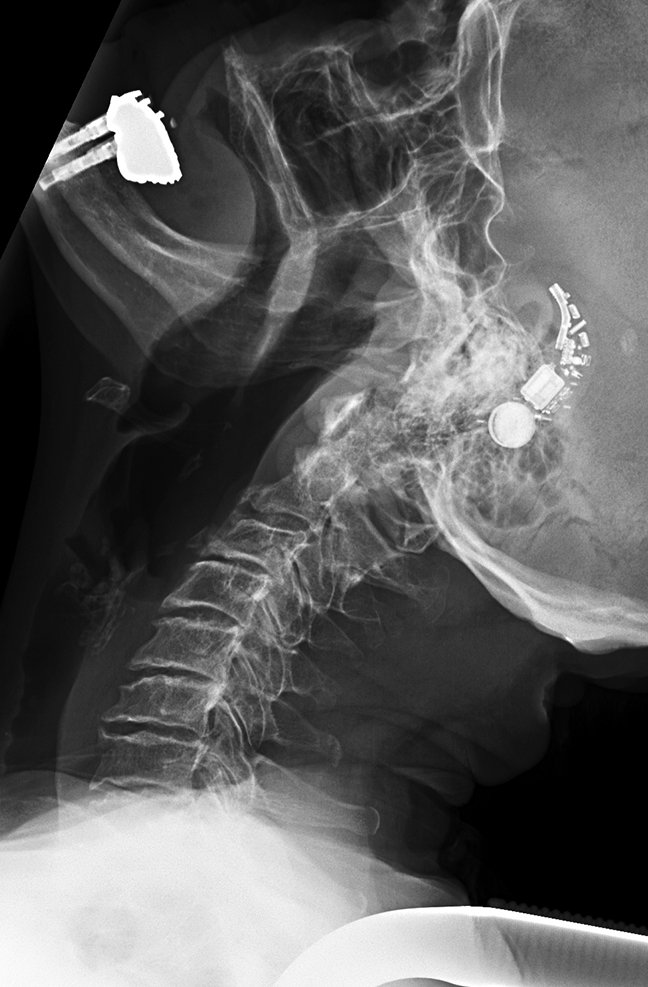

#CaseOfTheWeek‼️🥳‼️ ☢️🩻☠️Case#22☠️🩻☢️ #Mass 📲➡️➡️#Diagnosis❔❓❔ #FOAMRad #RadEd #MedEd #OrthoEd #OrthoTwitter @ssr_rwg @UWRadRes @ISSVA_org